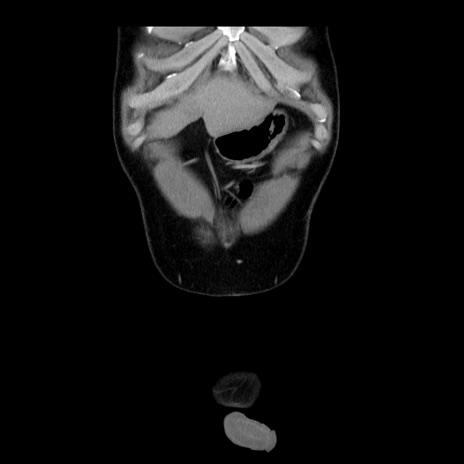

症例4(冠状断像)

【症例】30歳代男性

【主訴】腹痛、嘔吐

【現病歴】昨晩から突然の腹痛あり、その後嘔吐、軟便も出現。腹痛が改善しないため救急搬送となる。2日前にしめ鯖の食事歴あり。

【身体所見】意識清明、苦悶様、BP 135/90mmHg、BT 35.7℃、腹部:平坦、やや硬、心窩部〜臍部に自発痛、圧痛あり、筋性防御+、反跳痛-

【データ】WBC 8100、CRP 0.57